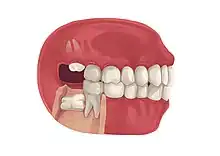

Impacted wisdom teeth is a condition where the third molars (wisdom teeth) are prevented from erupting into the mouth.[1] This can be caused by a physical barrier, such as other teeth, or when the tooth is angled away from a vertical position.[2] Completely unerupted wisdom teeth usually result in no symptoms, although they can sometimes develop cysts or neoplasms. Partially erupted wisdom teeth or wisdom teeth that are not erupted but are exposed to oral bacteria through deep periodontal pocket, can develop cavities or pericoronitis. Removal of impacted wisdom teeth is advised for the future prevention of or in the current presence of certain pathologies, such as caries (dental decay), periodontal disease or cysts. Prophylactic (preventative) extraction of wisdom teeth is preferred to be done at a younger age (middle to late teenage years) to take advantage of incomplete root development, which is associated with an easier surgical procedure and less probability of complications.[3]

Impacted wisdom teeth are often described by the direction of their impaction (forward tilting, or mesioangular being the most common), the depth of impaction and the age of the patient as well as other factors such as pre-existing infection or the presence of pathology (cysts, tumors or other disease).[5]: 143–144 Each of these factors is used to predict the difficulty (and rate of complications) when removing an impacted tooth, with age being the most reliable predictor[8] rather than the orientation of the impaction.[9]

Wisdom teeth become impacted when there is not enough room in the jaws to allow for all of the teeth to erupt into the mouth. Because the wisdom teeth are the last to erupt, due to insufficient room in the jaws to accommodate more teeth, the wisdom teeth become stuck in the jaws, i.e., impacted. There is a genetic predisposition to tooth impaction. Genetics plays an important, albeit unpredictable role in dictating jaw and tooth size and tooth eruption potential of the teeth. Some also believe that there is an evolutionary decrease in jaw size due to softer modern diets that are more refined and less coarse than our ancestors'.[6]